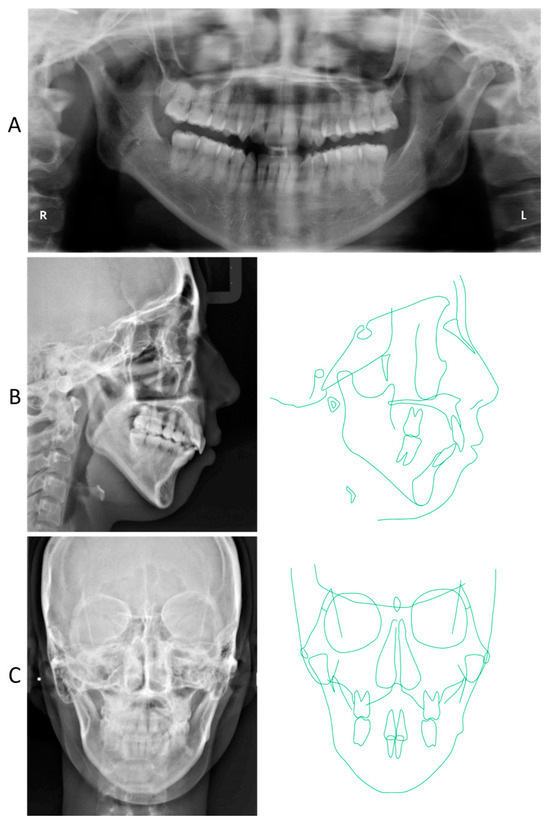

2. Detailed Case Description

2.4. Treatment Results